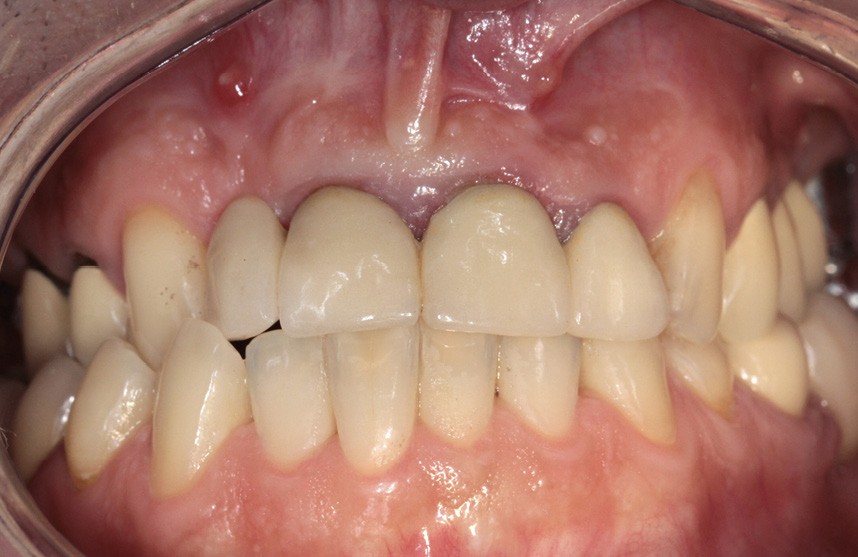

L’examen endobuccal montre deux fistules en regard des apex de 12 et 21 (fig. 1). Nous notons la présence d’une classe III squelettique, d’une occlusion inversée du côté droit (fig. 2) et des édentements non compensés au niveau de 26 et 36. L’orthopantomogramme révèle la présence d’une volumineuse lésion kystique qui s’étend de la 12 à la 22 (fig. 3).